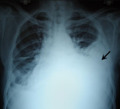

A pleural effusion appears as an area of whiteness on a standard posteroanterior chest X-ray.[7] Normally, the space between the visceral pleura and the parietal pleura cannot be seen. A pleural effusion infiltrates the space between these layers. Because the pleural effusion has a density similar to water, it can be seen on radiographs. Since the effusion has greater density than the rest of the lung, it gravitates towards the lower portions of the pleural cavity. The pleural effusion behaves according to basic fluid dynamics, conforming to the shape of pleural space, which is determined by the lung and chest wall. If the pleural space contains both air and fluid, then an air-fluid level that is horizontal will be present, instead of conforming to the lung space.[8] Chest radiographs in the lateral decubitus position (with the patient lying on the side of the pleural effusion) are more sensitive and can detect as little as 50 mL of fluid. At least 300 mL of fluid must be present before upright chest X-rays can detect a pleural effusion (e.g., blunted costophrenic angles).